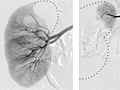

An angiogram is an X-ray test that uses dye and imaging (fluoroscopy) to take pictures of the blood flow in an artery or a vein. An angiogram can be used to look at the arteries or veins in the head, arms, legs, chest, back, or belly. This test is done to look for problems in the arteries or veins.

During an angiogram, the doctor will put a thin, flexible tube into a blood vessel in your groin or arm. This tube is called a catheter. The doctor guides the tube to the blood vessel that will be studied. Then a dye is injected through the tube to make the area easier to see. X-rays or pictures are taken of the area.